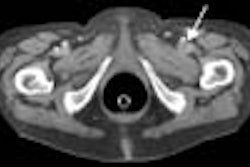

In today's Virtual Colonoscopy Digital Community you'll find another presentation from the recent 2005 European Congress of Radiology. Dr. Adrian Spreng from Bern, Switzerland, parses the extracolonic findings in two groups of VC patients -- one that received IV contrast before the exam, and one that did not.